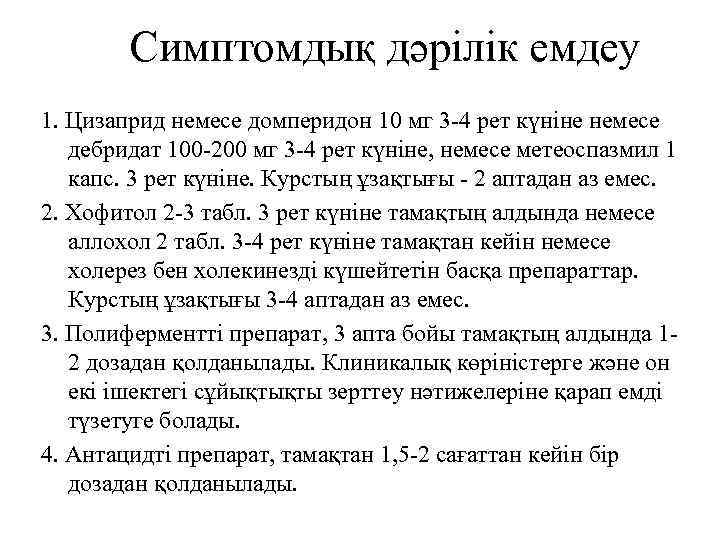

Симптомдық дәрілік емдеу 1. Цизаприд немесе домперидон 10 мг 3 -4 рет күніне немесе дебридат 100 -200 мг 3 -4 рет күніне, немесе метеоспазмил 1 капс. 3 рет күніне. Курстың ұзақтығы - 2 аптадан аз емес. 2. Хофитол 2 -3 табл. 3 рет күніне тамақтың алдында немесе аллохол 2 табл. 3 -4 рет күніне тамақтан кейін немесе холерез бен холекинезді күшейтетін басқа препараттар. Курстың ұзақтығы 3 -4 аптадан аз емес. 3. Полиферментті препарат, 3 апта бойы тамақтың алдында 12 дозадан қолданылады. Клиникалық көріністерге және он екі ішектегі сұйықтықты зерттеу нәтижелеріне қарап емді түзетуге болады. 4. Антацидті препарат, тамақтан 1, 5 -2 сағаттан кейін бір дозадан қолданылады.